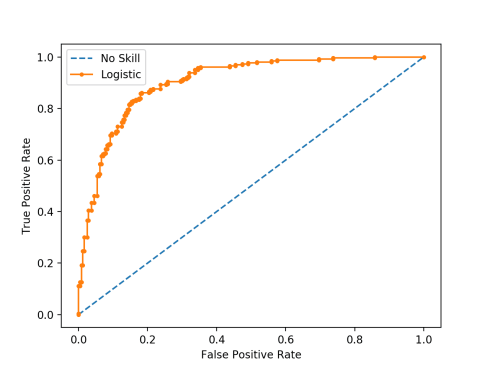

منحنی ROC چیست؟

منحنی ROC یا Receiver Operating Characteristic چیست؟ منحنی مشخصه عملکرد، که به اختصار به آن منحنی[بیشتر بخوانید]